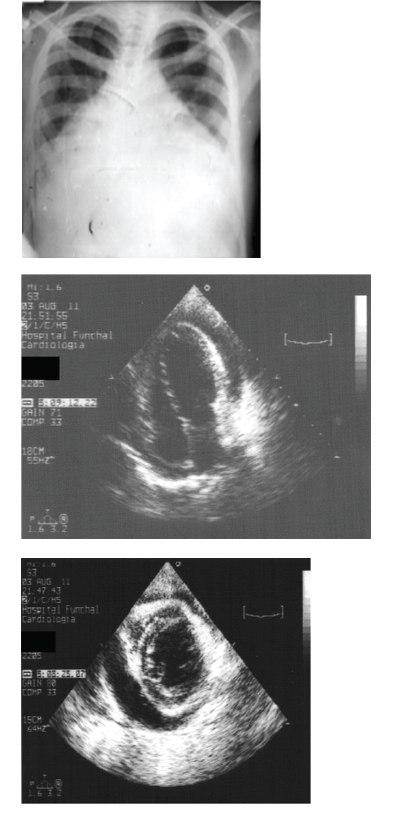

Observe as imagens abaixo,respectivamente de um RX de tórax em Pa,um ecocardiograma corte apical, e corte transversal do mesmo paciente.

Nesse caso, é correto afirmar que: